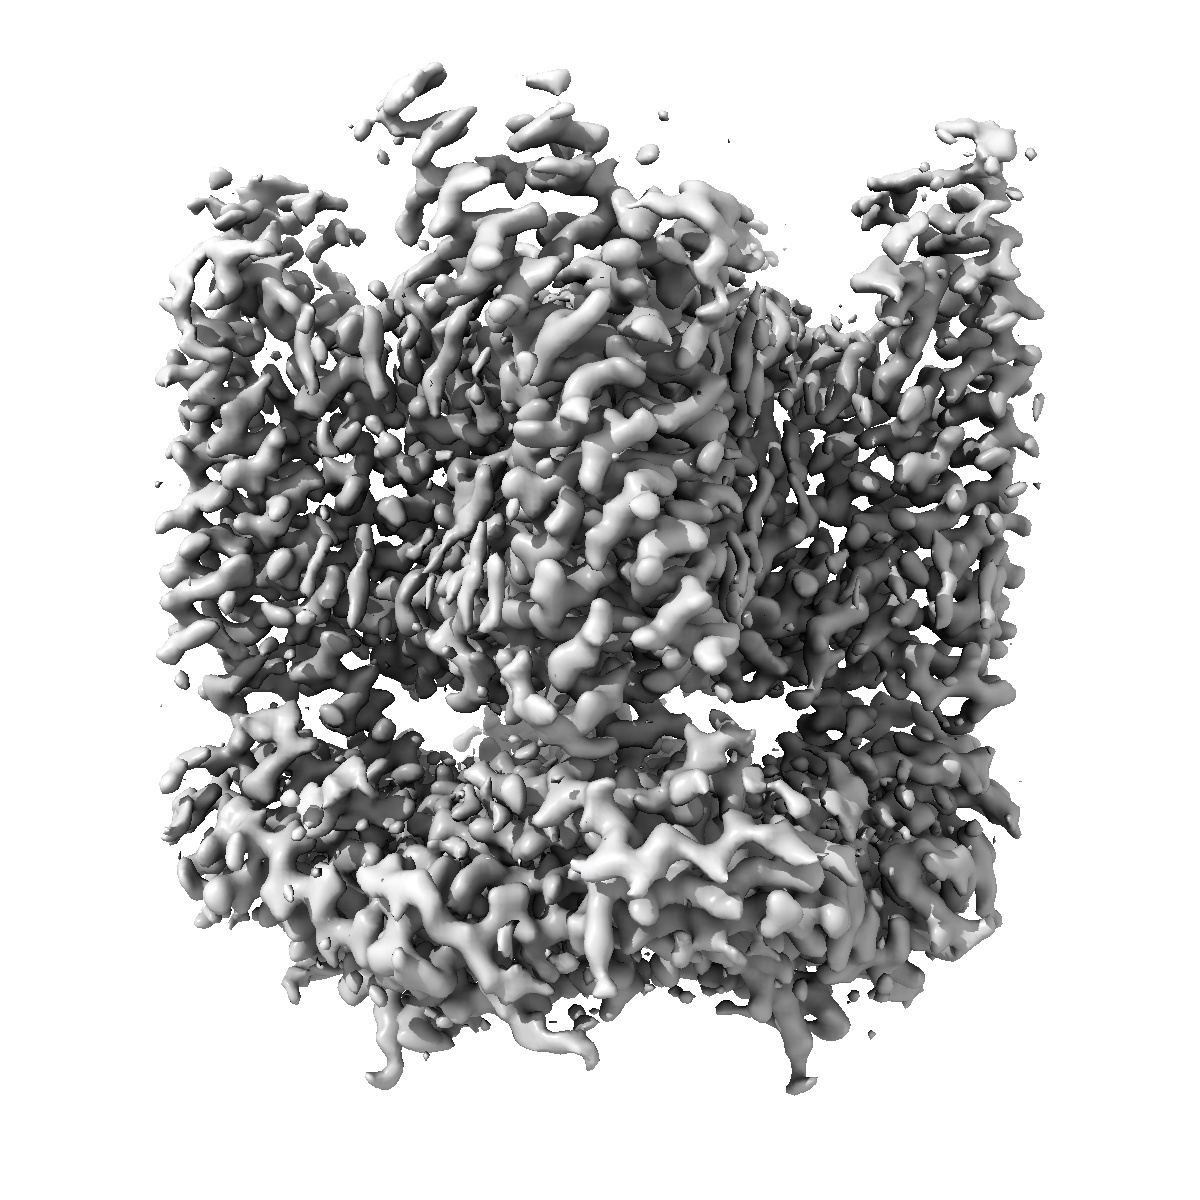

TRPML1 in complex with compound 9a

Single-particle2.4 Å

Sample: Mucolipin-1

High throughput cryo-EM provides structural understanding for modulators of the lysosomal ion channel TRPML1.

(2025) Structure , 33 , 1374 - 1385.e7